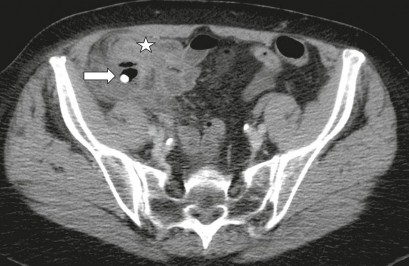

Hình 1.7: Hình ảnh VRTC có vôi hóa, hình thành ổ áp xe [35]